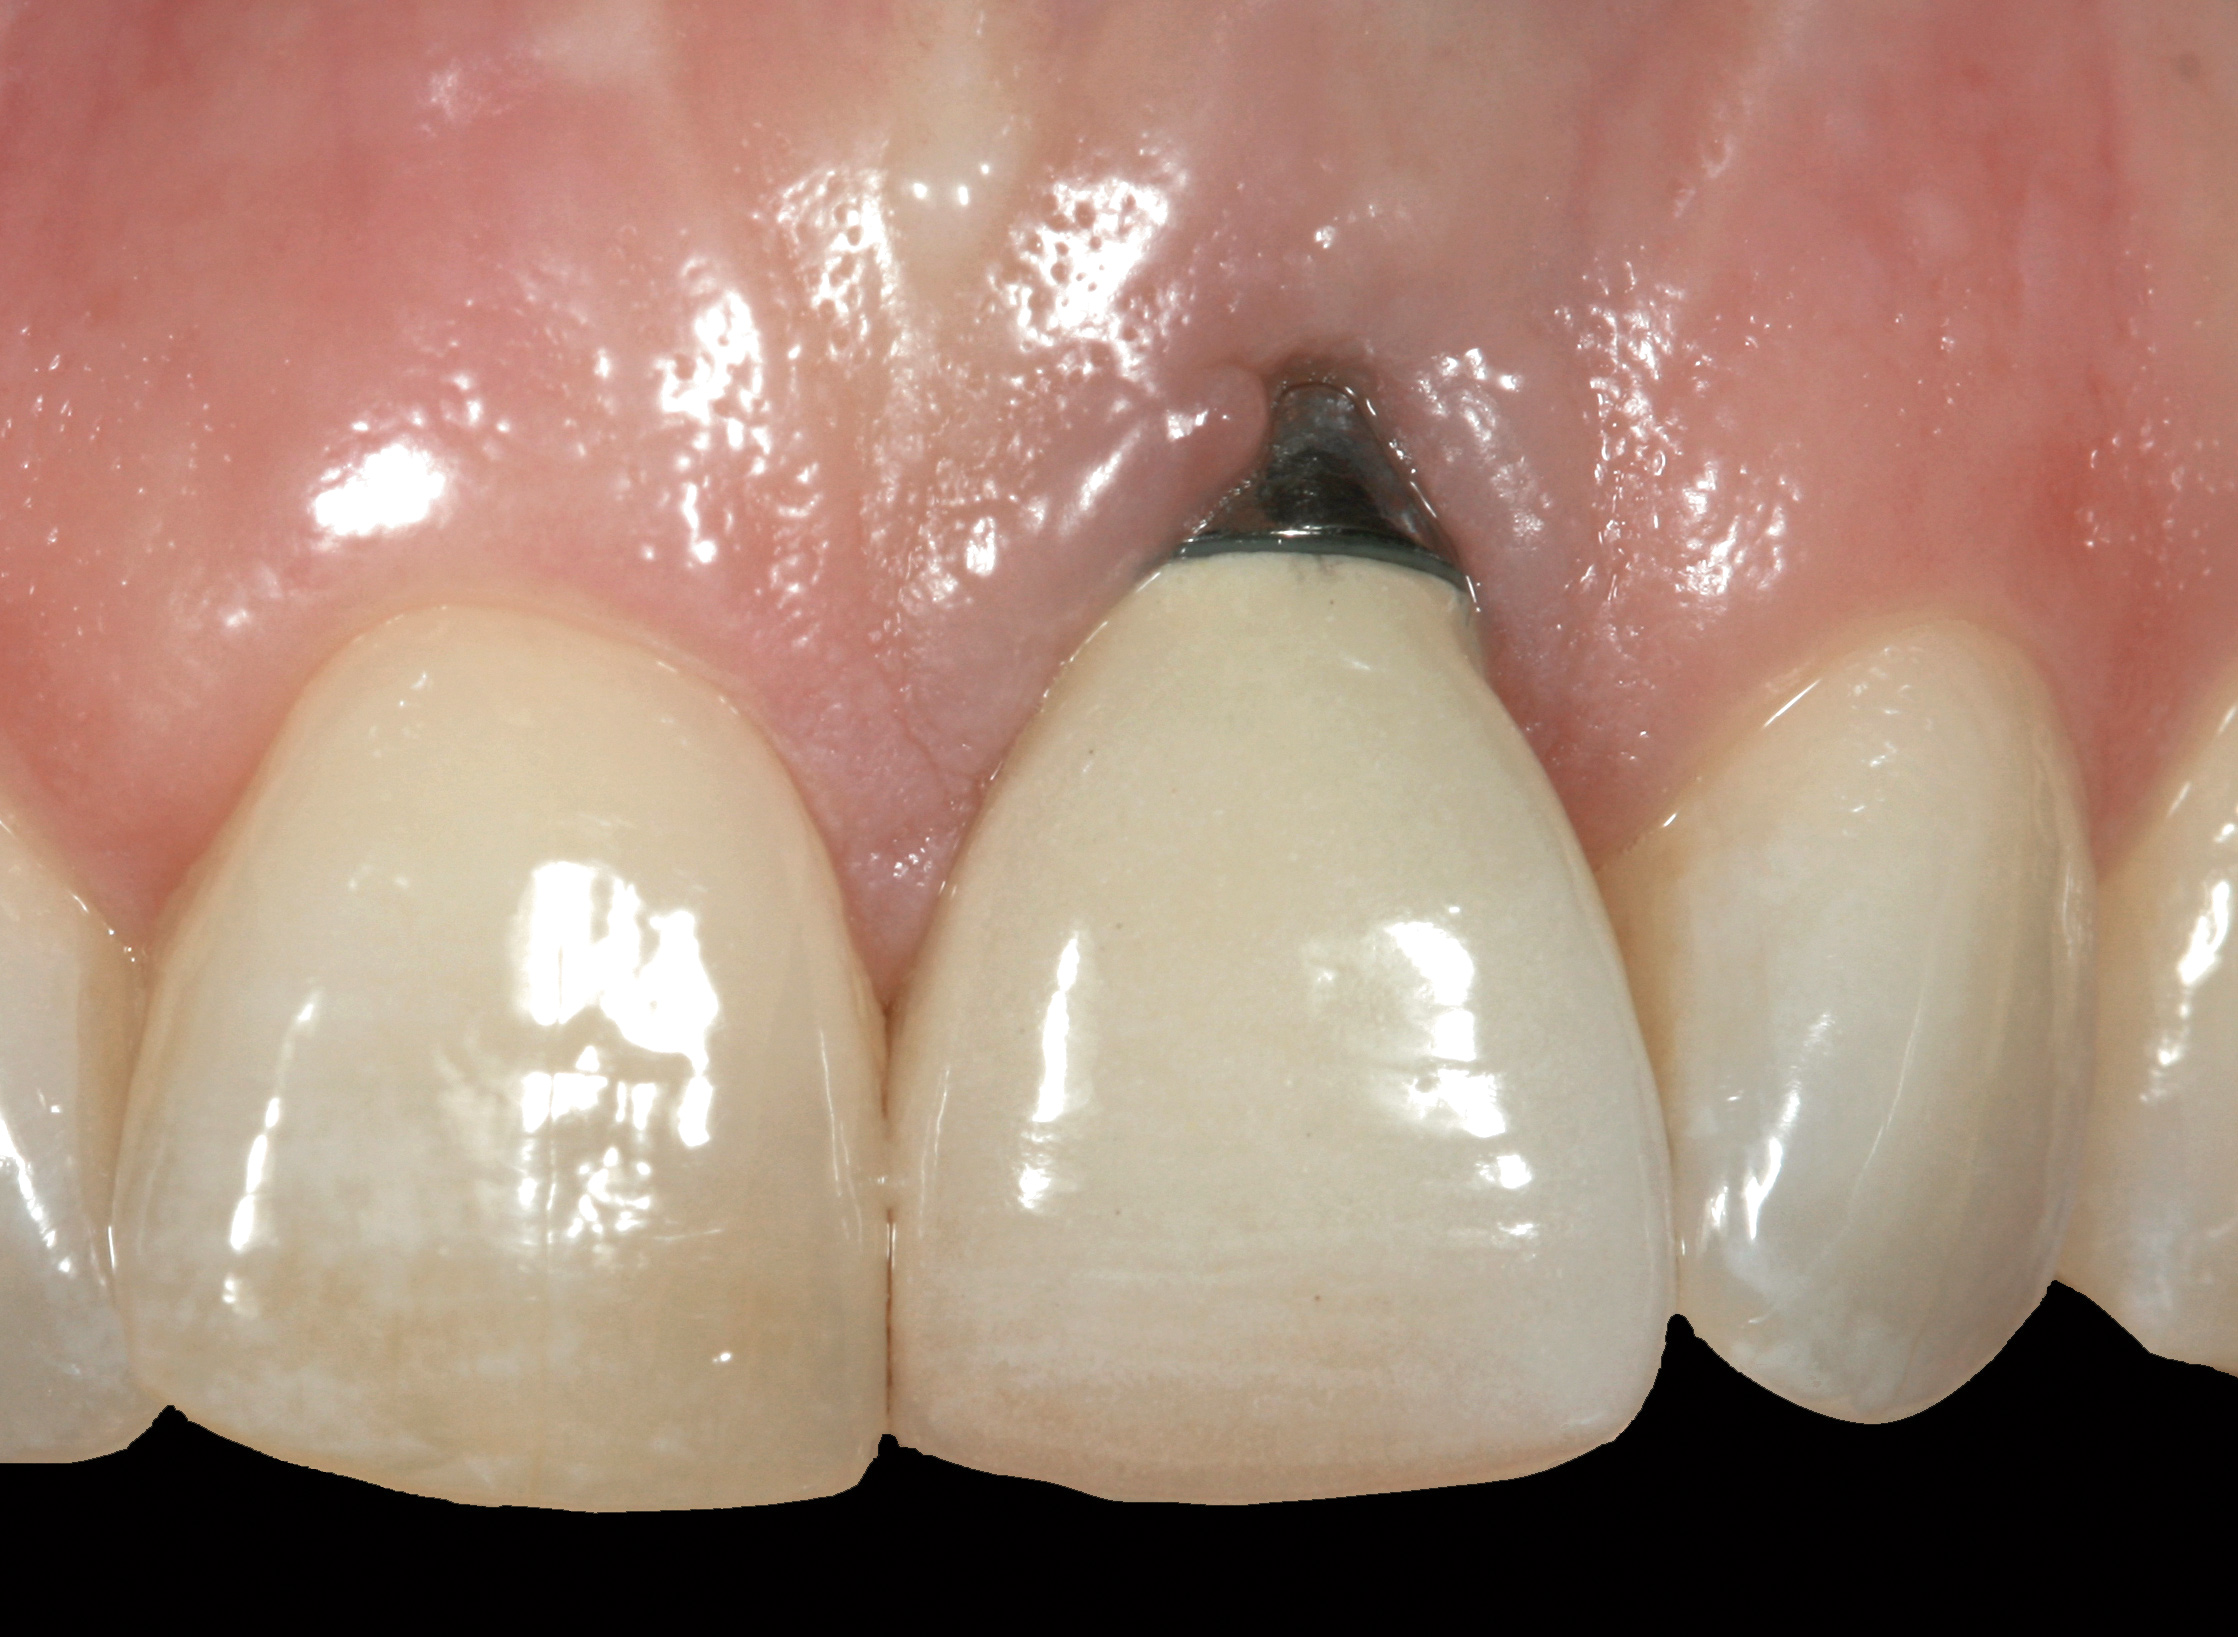

Fig 36. Two weeks after RBR placement, the soft tissue did not adequately cover the implant. The problem was in poor implant angulation and proper depth to allow the soft tissues to cover over.

Figure 36

The crown and screw-retained custom abutment were removed, and a surgical cover screw was placed into the implant, thereby allowing spontaneous gingival augmentation in situ (Figure 33 and Figure 34). Note that the lingual aspect of the implant site was significantly more coronal than the labial aspect, which was positive because the defect would be limited to a facial–lingual defect. A fixed RBR bridge was cemented on the adjacent teeth and used as a tooth-supported transitional provisional restoration (Figure 35). A few weeks were allotted to let the soft tissue heal and migrate around the cover screw (Figure 36) to see if there would be complete coverage, thereby allowing a soft-tissue augmentation procedure to be performed with primary flap closure as in clinical scenario No. 2. The major obstacle in achieving a positive tissue response was that the implant depth was also deficient because the implant–abutment connection was at the level of the free gingival margin. It was decided that the best treatment option would be to remove the implant. A high-powered reverse-torque device (Fixture Remover Kit, NeoBiotech, www.neobiotechus.com) was used to remove the implant atraumatically (Figure 38 through Figure 41). The implant socket was allowed to heal for several months not unlike an extracted tooth (Figure 42). A new implant was placed in a better position from both a restorative and esthetic perspective (Figure 43), and after a few months of healing, a new crown was made (Figure 44). A satisfactory functional and esthetic result was achieved (Figure 45 and Figure 46) without employing pink porcelain.